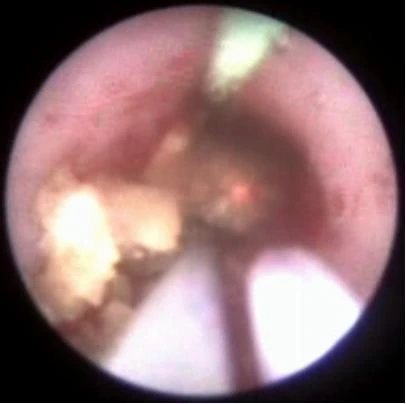

Через рабочий канал уретеропиелоскопа проводится лазерное волокно. По оптическому каналу изображение от эндоскопа передается на монитор. Волокно вплотную подводится к камню и при нажатии на педаль подаётся лазерное излучение, вследствие которого происходит деструкция камня.

Добившись нужной дисперсности фрагментов камня, их элиминируют корзинкой, либо другими видами экстракторов (петли, щипцы). Производится эндоскопическая ревизия мочеточника. Подтверждается полное удаление фрагментов камня. Уретеропиелоскоп удаляется.